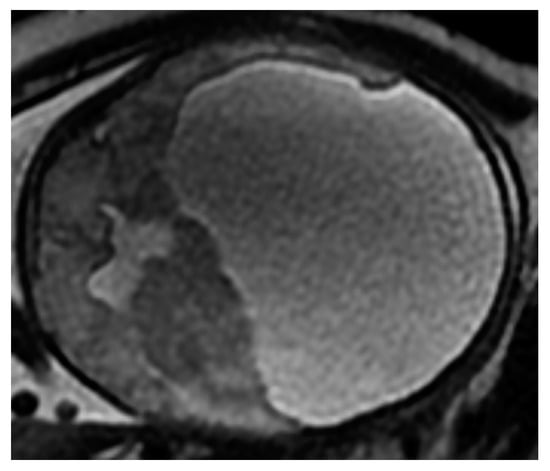

3.2.3. Defects of the Posterior Fossa

Defects of the Cerebellum

Dandy-Walker Syndrome

Arnold-Chiari Syndrome

Arachnoid Cyst